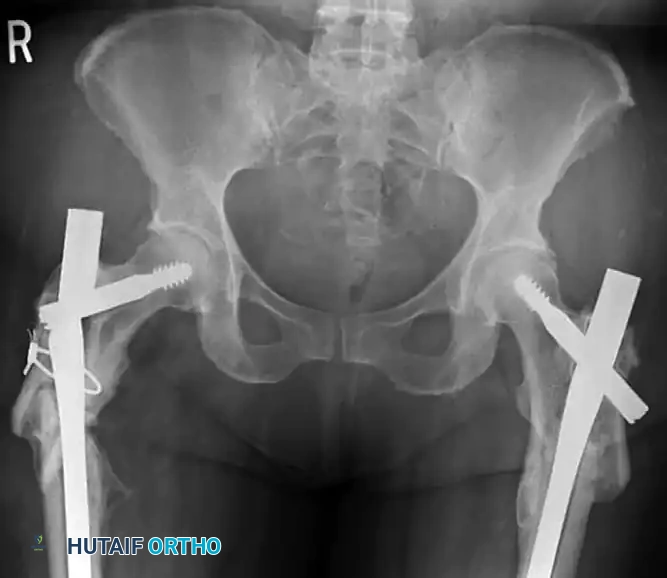

Varus Malalignment and Implant Failure

The most devastating complication of PFLP fixation in the subtrochanteric region is varus collapse leading to catastrophic implant failure. This typically occurs due to a failure to restore the medial cortical buttress or an improper starting point/trajectory that places the implant too far laterally, increasing the bending moment on the plate.

Figure H: Radiographic example of severe varus malalignment with subsequent implant failure resulting from a lateral starting point and inadequate medial support.